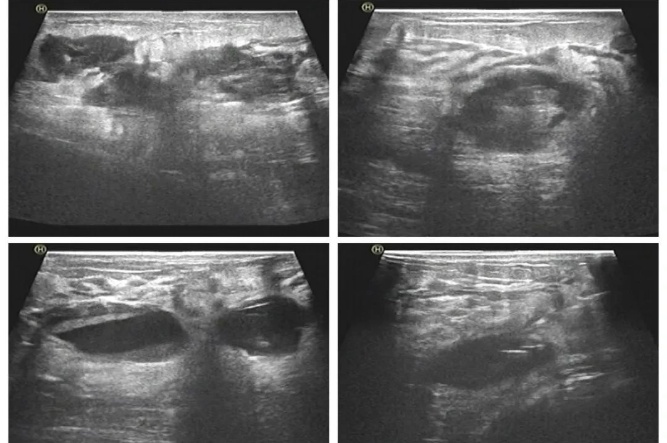

25歲的小美剛沉浸在當(dāng)媽媽的喜悅中,但哺乳期右側(cè)乳房突發(fā)疼痛、紅腫,摸上去感覺有包塊,小美心中惴惴不安,急忙來到晉城大醫(yī)院尋求治療。超聲檢查顯示:右側(cè)乳腺可見范圍約8.6cm×4.5cm膿性包塊。

一周后,28歲的寶媽小麗哺乳期頂著高燒來到醫(yī)院超聲醫(yī)學(xué)中心,左側(cè)乳房脹痛難忍,超聲檢查:左側(cè)乳腺可見多發(fā)的膿性包塊,較大范圍約4.5cm×3.6cm。

與小美不同的是,小麗因整個(gè)乳腺膿腔較多,且每個(gè)膿腔互不相通,不具備置管引流的條件,經(jīng)超聲醫(yī)學(xué)中心會(huì)診,決定另辟蹊徑,超聲引導(dǎo)下逐個(gè)膿腔進(jìn)行抽吸及沖洗。第一次抽吸3個(gè)膿腔,患者疼痛明顯減輕,隨后一周內(nèi),分次抽吸膿腔達(dá)10余個(gè)??倸v時(shí)兩周,小麗已經(jīng)痊愈,同樣是無“瘢痕”,寶媽甚是開心。